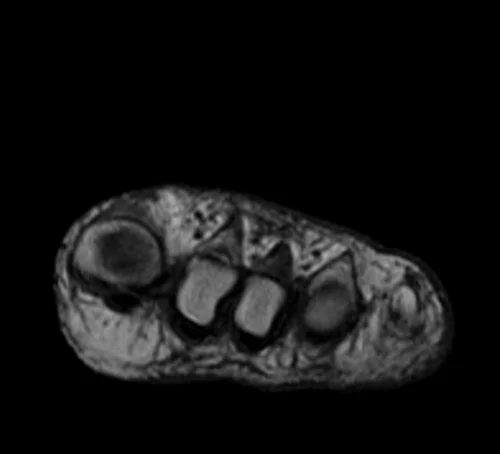

MRI FOOT AXIAL T1 IMAGE 2 - MRI